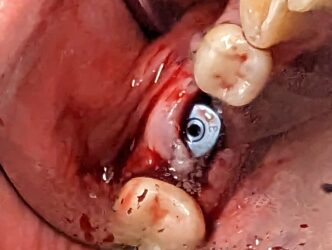

Hey guys just wanted to get to know your thoughts on what I can do to improve. This is a 78 yr old patient with controlled diabetes/hypothyroid/high BP. She takes her medications regularly and reports to be controlled. #29 was extracted due to fracture in October 2022 with bone graft. Implant Astra Osseospeed EV size 3.6×9 was placed in…

I created a deeper osteotomy today and placed a larger longer implant after removing the failed implant and thoroughly curetting and irrigating with CHX. Any guidance and feedback is welcome.